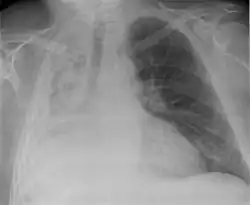

Pleural effusion

A pleural effusion is an accumulation of fluid inside the pleural space. If this collection of fluid gets large enough, it can also push structures in the chest away from it and cause a mediastinal shift. However, a pleural effusion can also pull the mediastinal structure towards itself. If this is the case, then there is an underlying condition causing the collapse of the lung on that side. An example is a tumor obstructing a bronchus and causing lung collapse and pleural effusion.[3]